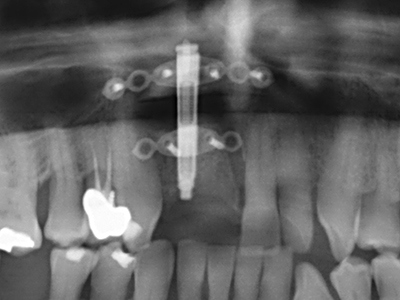

Indication: Bone splitting

Bone tissue is not simply a mineral structure but also contains a substantial proportion of collagen fibres. This means it not only has good compressive strength but also a degree of flexibility, which can be taken advantage of when performing bone augmentations. In the classical expansion procedure using bone splitting, the atrophied alveolar ridge is split longitudinally and carefully expanded after reaching an adequate osteotomy depth (Fig. 13-16), ideally without substantial removal of the periosteum (Brugnami, Caiazzo et al. 2014, Stricker, Fleiner et al. 2014). Screw and plate systems with increasing expansion distance have proven effective in separating the two bone lamellae while remaining below the fracture threshold. In general, residual bone widths of at least 3–4 mm are required (Chiapasco, Zaniboni et al. 2006) to guarantee adequate flexibility and sufficient bone coverage of the future implants. If necessary, a vertical relief osteotomy on one or both sides can improve flexibility. A combination with additional augmentation techniques, particularly on the buccal side, has been described as an alternative to the classical technique.

The splitting procedure is particularly atraumatic and there is no significant loss of dimension when using piezosaws, and there are no significant differences between implants in split jaws and implants in an alveolar ridge without a bone deficit (Chiapasco, Zaniboni et al. 2006, Danza, Guidi et al. 2009). However, sufficient continuous irrigation is essential, particularly with locally restricted and deep splitting to prevent thermal stress in the apical osteotomy regions.